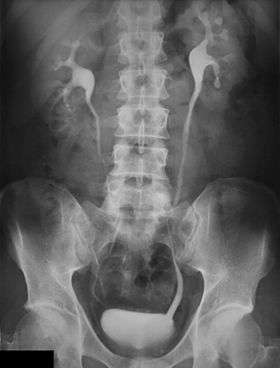

An intravenous pyelogram (IVP), also called an intravenous urogram (IVU), is a radiological procedure used to visualize abnormalities of the urinary system, including the kidneys, ureters, and bladder. Unlike a kidneys, ureters, and bladder x-ray (KUB), which is a plain (that is, noncontrast) radiograph, an IVP uses contrast to highlight the urinary tract.

In IVP, the contrast agent is given intravenously, allowed to be cleared by the kidneys and excreted through the urinary tract as part of the urine. If this is contraindicated for some reason, a retrograde pyelogram, with the contrast flowing upstream, can be done instead.

An injection of X-ray contrast medium is given to a patient via a needle or cannula into the vein, typically in the antecubital fossa of arm. The contrast is excreted or removed from the bloodstream via the kidneys, and the contrast media becomes visible on X-rays almost immediately after injection. X-rays are taken at specific time intervals to capture the contrast as it travels through the different parts of the urinary system. This gives a comprehensive view of the patient's anatomy and some information on the functioning of the renal system.

Immediately after the contrast is administered, it appears on an X-ray as a 'renal blush'. This is the contrast being filtered through the cortex. At an interval of 3 minutes, the renal blush is still evident (to a lesser extent) but the calyces and renal pelvis are now visible. At 9 to 13 minutes the contrast begins to empty into the ureters and travel to the bladder which has now begun to fill. To visualize the bladder correctly, a post micturition X-ray is taken, so that the bulk of the contrast (which can mask a pathology) is emptied.